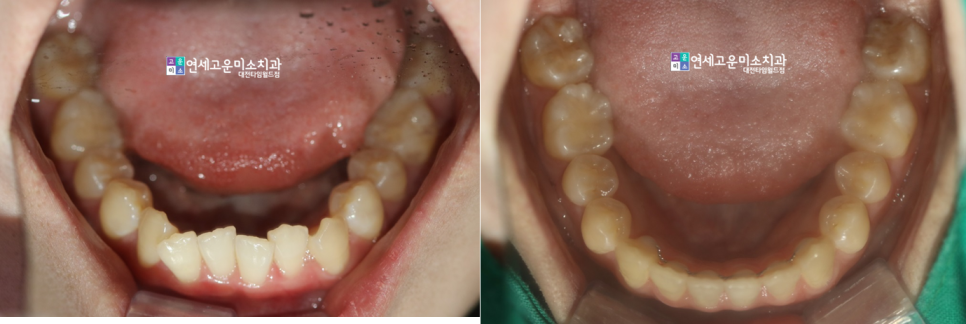

치료가 끝난 이후의 모습입니다.

완치에 이르기까지는 대략

2년 정도가 소요되었습니다

(2021. 3. ~ 2023. 1.)

단순하게 앞니만 배열하기보다는

전반적인 부정교합을 어떻게

정상적으로 만들 것인가에 대해

충분히 고민하고 치료해야 합니다.

전후를 비교해보았습니다.

배열이 잘 마무리되었으며

중심선도 정확히 일치시켰습니다.

교정이 끝나고 나서 치아가 아주

건강해 보이는 느낌입니다.

저는 교정 후 이런 모습이 좋습니다^^